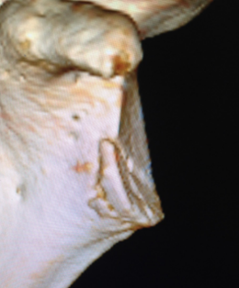

全镜下Latarjet手术